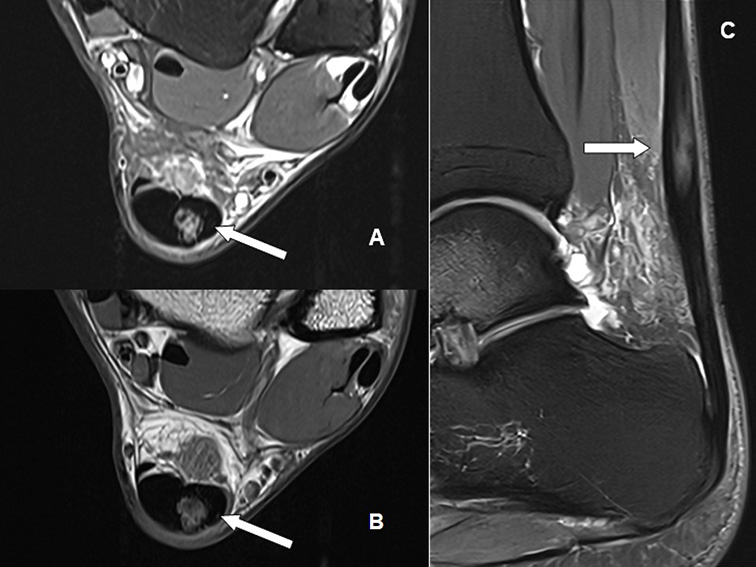

In the Achilles’ tendon magnetic resonance imaging (MRI) (Figure 5), axial T2-weighted sequences with fat saturation, axial T1-weighted sequences, and sagittal T2-weighted sequences with fat saturation identified intermediate signal tissue filling the area corresponding to the partial tear in the tendon body, confirming the structural finding previously observed.

Figure 5. Magnetic resonance imaging of the Achilles’ tendon

Axial T2-weighted sequence with fat saturation (A); axial T1-weighted sequence (B), and sagittal T2-weighted sequence with fat saturation (C). Note the intermediate signal tissue filling the partial tear area in the Achilles tendon body (white arrows).